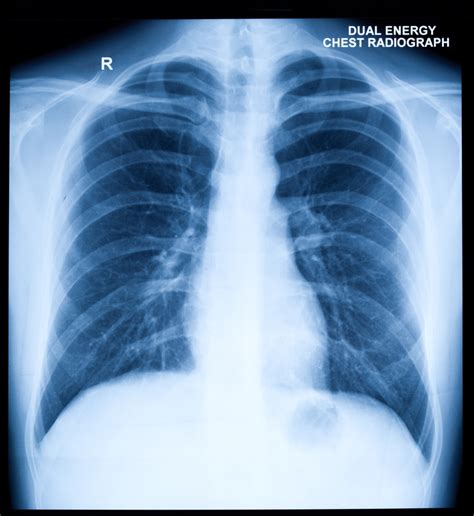

A chest X-ray, or radiograph, uses a small amount of radiation to create images of the inside of your chest, including your heart, lungs, and blood vessels. For suspected mesothelioma, doctors are particularly keen on observing the pleural lining, the membrane surrounding your lungs.

While a chest X-ray can't definitively diagnose mesothelioma, it can reveal certain abnormalities that suggest its presence. These might include:

- Pleural Thickening: A visible thickening of the lung lining, often calcified (pleural plaques), which is a common sign of past asbestos exposure and a risk factor for mesothelioma.

- Pleural Effusion: An accumulation of fluid between the layers of the pleura, which can cause shortness of breath. This is a very common finding in mesothelioma.

- Nodules or Masses: Any unusual growths or shadows on the lung or pleural surface.

- Loss of Lung Volume: In advanced cases, the disease can constrict the lung, reducing its overall size.

It's important to remember that these findings aren't exclusive to mesothelioma. Other conditions can also cause similar changes, which is why further tests are almost always needed.